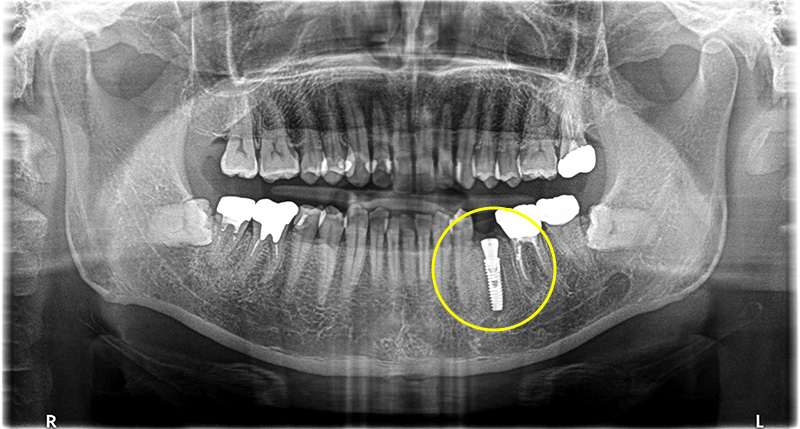

医院全体で1000本以上の実績

安心のインプラント治療

当院では1000本を超えるインプラント治療の実績に基づき、CTによる精密な診断のもと、安全性を優先した治療計画を立案します。 骨造成など難度の高い症例にも対応可能です。 失われた歯の機能と見た目を取り戻すための、良質な方法をご提案します。